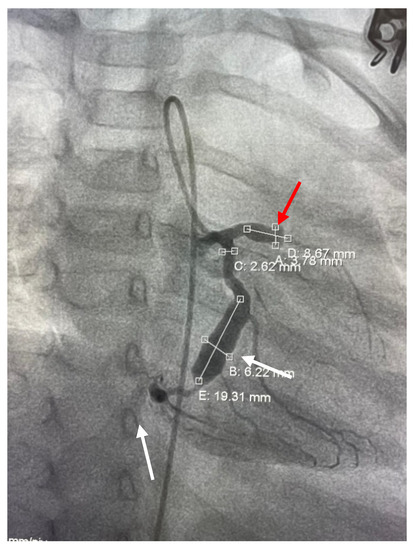

2. Case Report